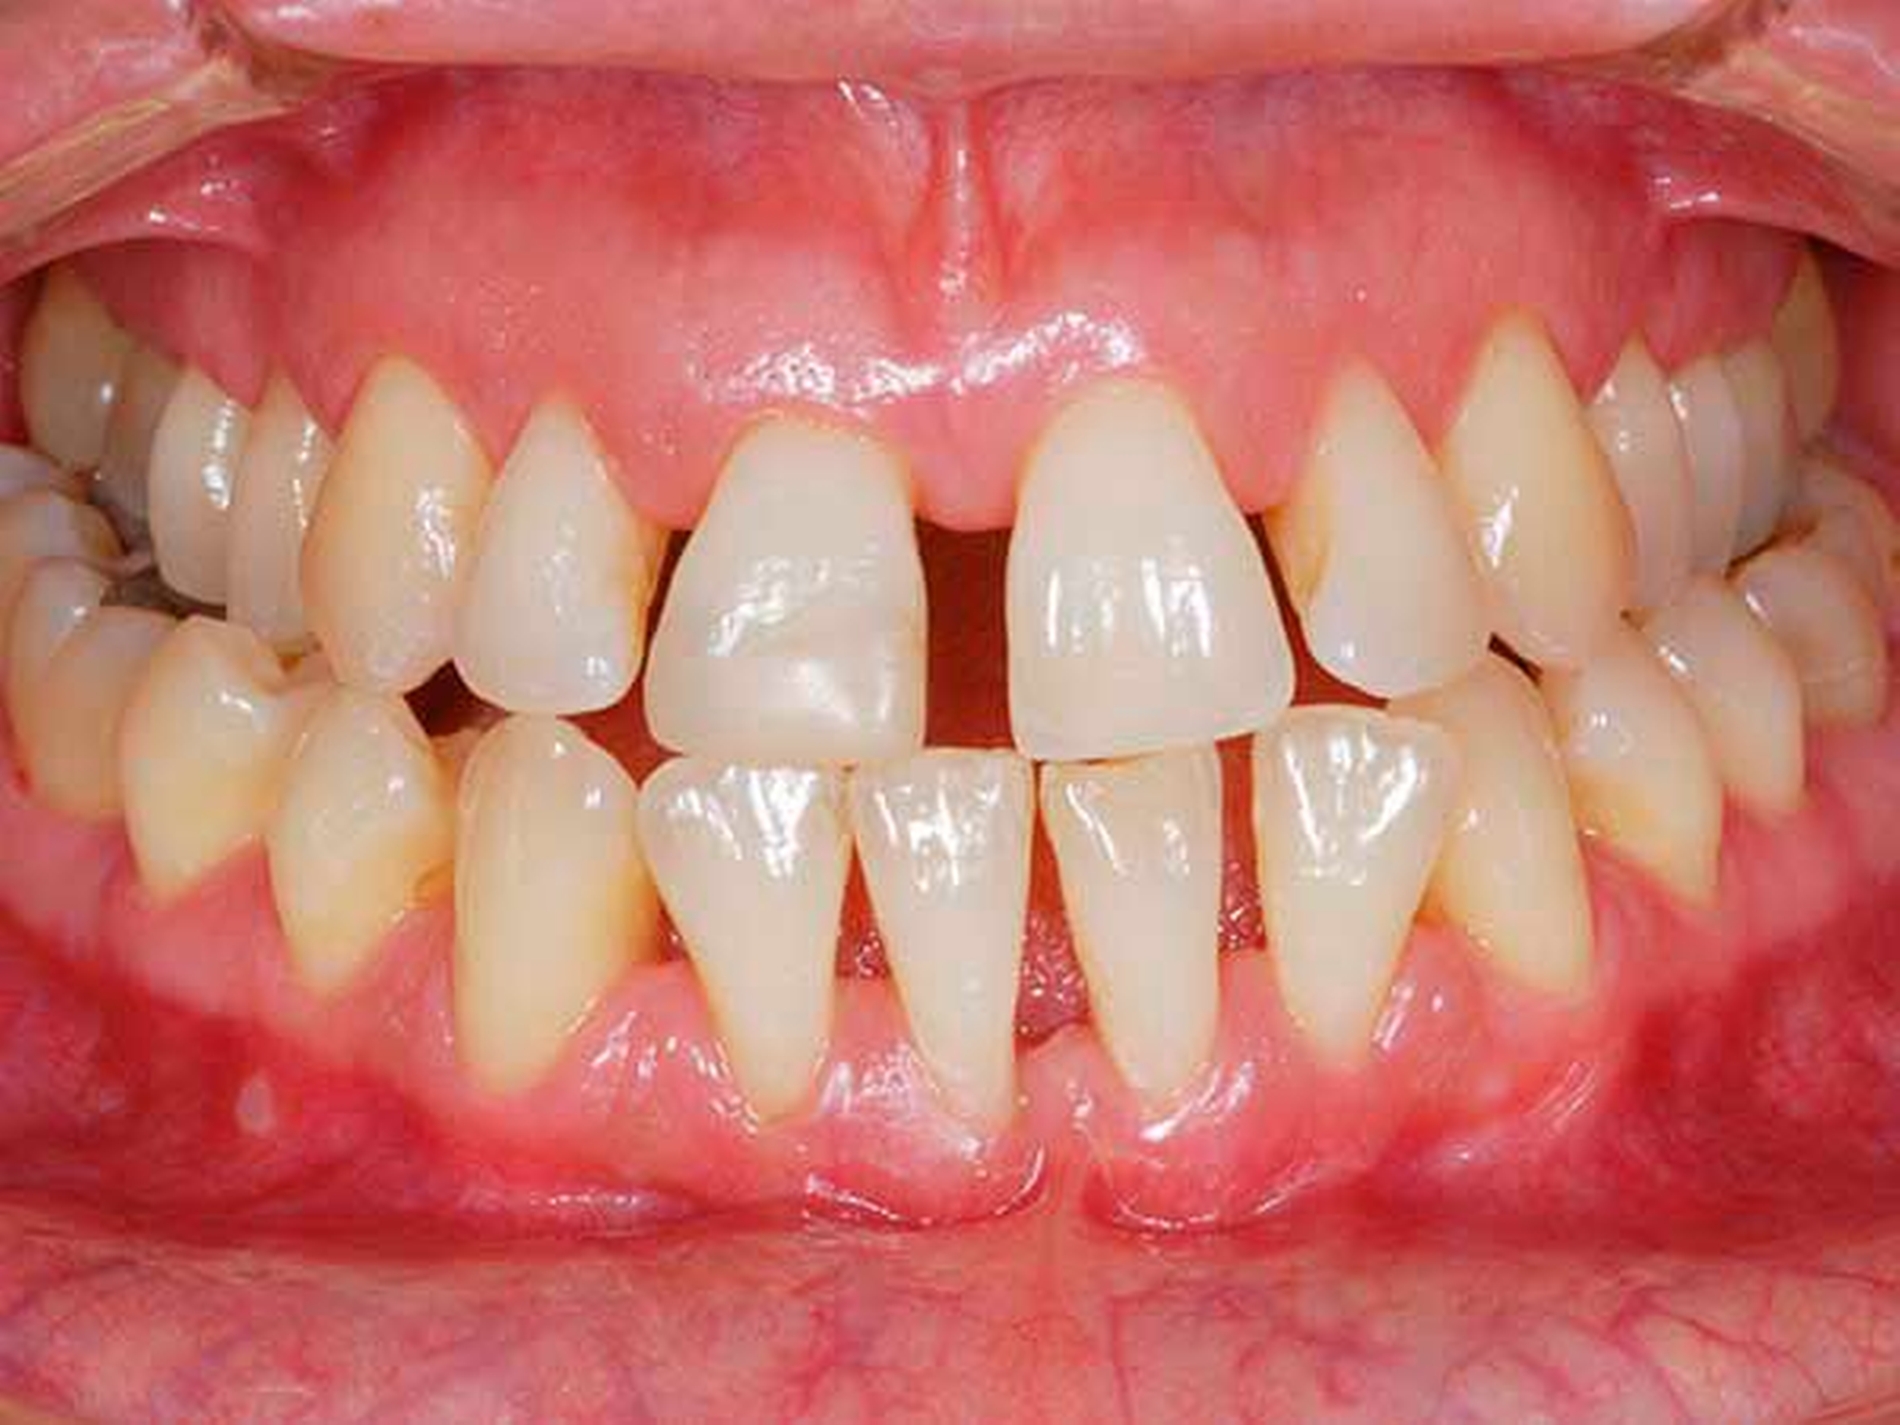

Die Empfänglichkeit eines Patienten wird durch verschiedene modifizierbare (nicht ausreichende Mundhygiene, Rauchen, Adipositas, schlecht eingestellter Diabetes mellitus, aber auch lokale Faktoren wie überstehende Kronenränder, schlecht pflegbare Restaurationen) und nicht modifizierbare (genetische/epigenetische Prädisposition, systemische Erkrankungen) Risikofaktoren moduliert [Lertpimonchai et al., 2017; Aarabi et al., 2017; Gaio et al., 2016; Knight et al., 2016].

Der Kern der ursachenbezogenen Therapie der Parodontitis liegt in der möglichst effizienten Entfernung des subgingivalen Biofilms und der gleichzeitigen Reduktion der modifizierbaren Risikofaktoren [Laleman et al., 2017]. Von wesentlicher Bedeutung ist in dieser Behandlungsphase eine ausführliche Motivation und Instruktion des Patienten mit dem Ziel einer individuell optimierten häuslichen Mundhygiene und der Herstellung einer Compliance. Hierfür haben sich Mundhygiene-Sitzungen bewährt, bei denen neben einem ausführlichen Mundhygienetraining auch eine Entfernung von supra-gingivalen und gingivalen harten und weichen Belägen sowie gegebenenfalls von vorhandenen lokalen irritierenden Faktoren erfolgt, um dem Patienten die Etablierung einer optimierten Mundhygiene zu erlauben.